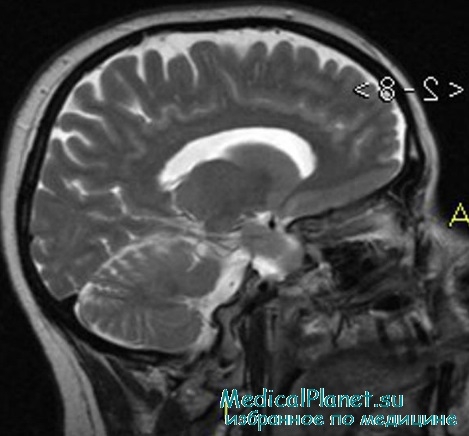

Внутричерепная гипотензия: КТ-исследования и их интерпретация

Раздел: Образы вокруг